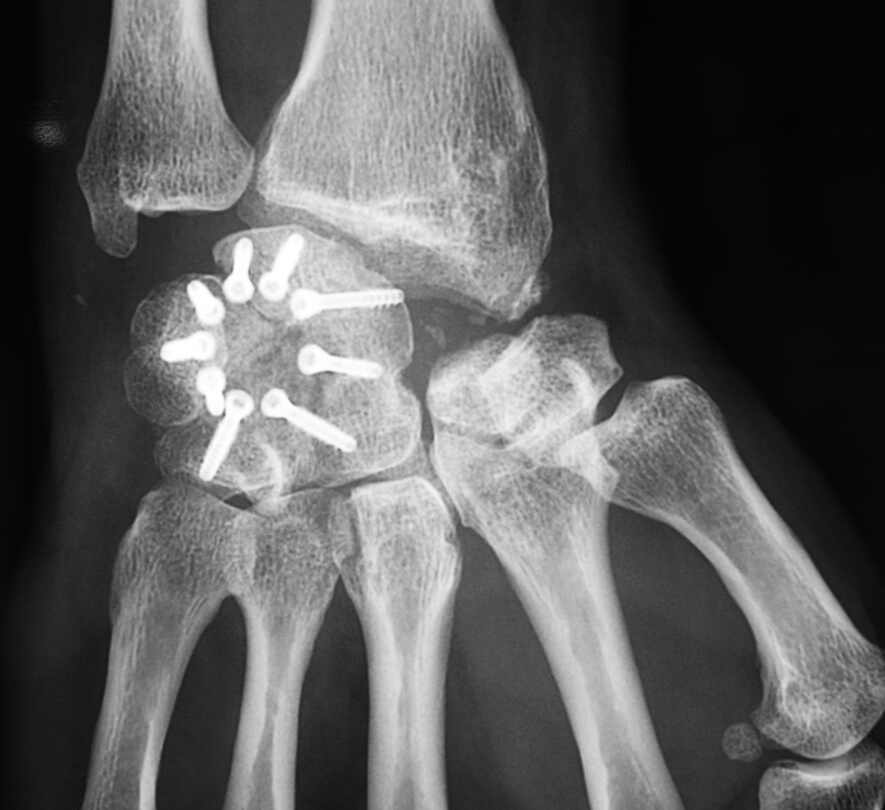

L’arthroscanner Est Demandé Dans Le Cadre Du Bilan Préopératoire Pour Évaluer Les Surfaces Articulaires Qui Peuvent Être Conservées Et Orienter Nos Choix Thérapeutiques.

L’arthrose Du Poignet Est Le Plus Souvent Secondaire À Une Séquelle Traumatique Ou Une Maladie Métabolique Et Concerne Habituellement La Région Périscaphoïdienne (Os Scaphoïde).